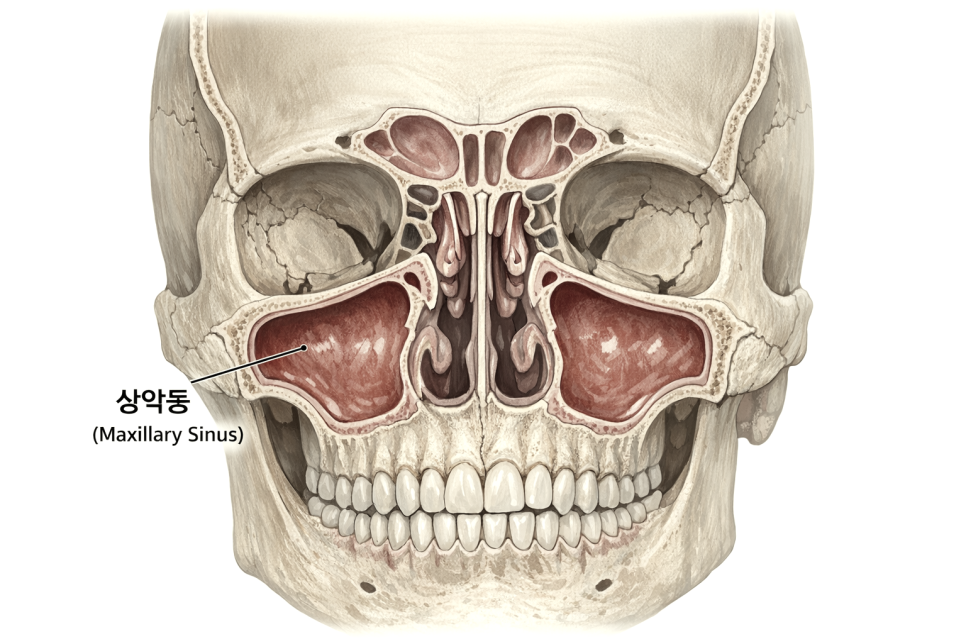

상악동이란

상악동(maxillary sinus)은 위턱뼈 안에 있는

빈 공간입니다.

코 옆쪽 광대뼈 부근

어금니 뿌리 위쪽에 위치하며

좌우 양쪽에 하나씩 있습니다.

부비동 중 하나인 이 공간은

두개골의 무게를 줄여주고

목소리의 울림에 관여하며

호흡 시 공기를 가습하는 역할을 합니다.

다만 위쪽 어금니 뿌리 근처에

위치해 있어 이 부위에 임플란트를 할 때는

상악동이라는 구조물을 조심해야 됩니다.